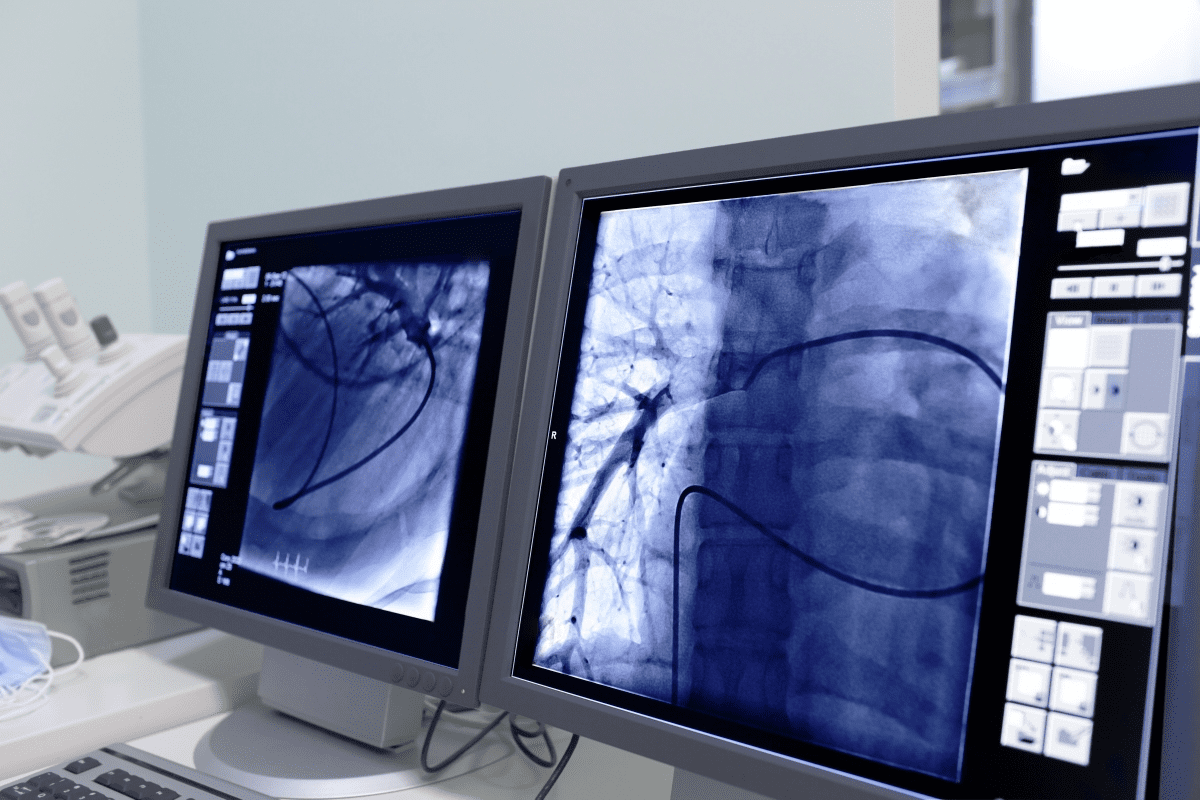

A PET scan is a test that uses nuclear medicine to diagnose health issues. It shows how active different parts of the body are. This is key for finding and treating diseases.

PET scans detect energy from a special tracer injected into the body. This tracer is a sugar molecule with a radioactive atom. It builds up in the body and emits positrons, which create gamma rays.

The PET scanner catches these gamma rays. It makes detailed images of the body’s inner workings. This is thanks to nuclear medicine, which uses small amounts of radioactive materials for diagnosis and treatment.

PET scans are special because they show how the body’s parts are working. They don’t just look at structure.

How PET Scans Differ from Other Imaging Tests

PET scans are different from CT scans or MRI. While CT and MRI show body structure, PET scans reveal metabolic activity. This makes them great for: